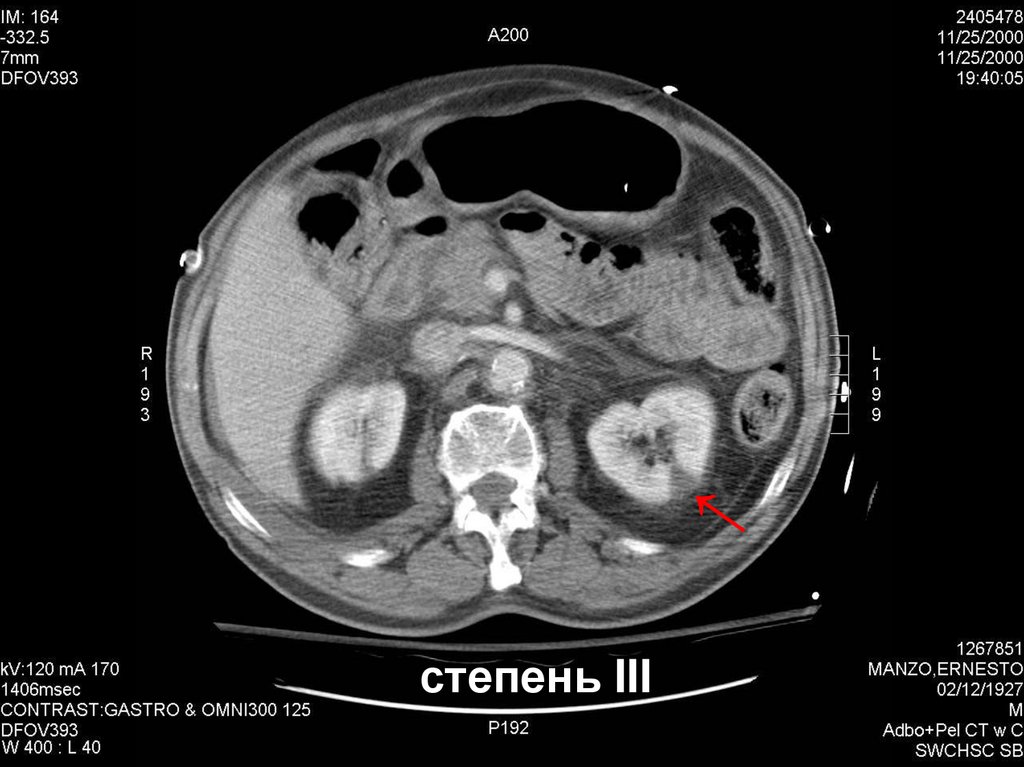

14.

степень III

15.

Разрыв почки с проникновением в ЧЛС

16.

Разрыв почки с повреждением сосудов

17.

РАЗРЫВ ЛМС

18.

степень IV